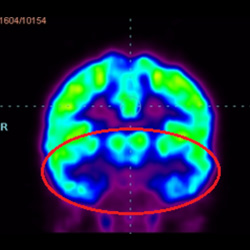

腦癱細胞療法, 腦癱治療

細胞治療前PET CT掃描顯示神經(jīng)組織中的藍/黑色區域,表明腦癱引起的大腦損傷。

細胞治療后,藍色和黑色區域減少,并且看到更活躍的區域。這表明損傷減少并改善了大腦功能。